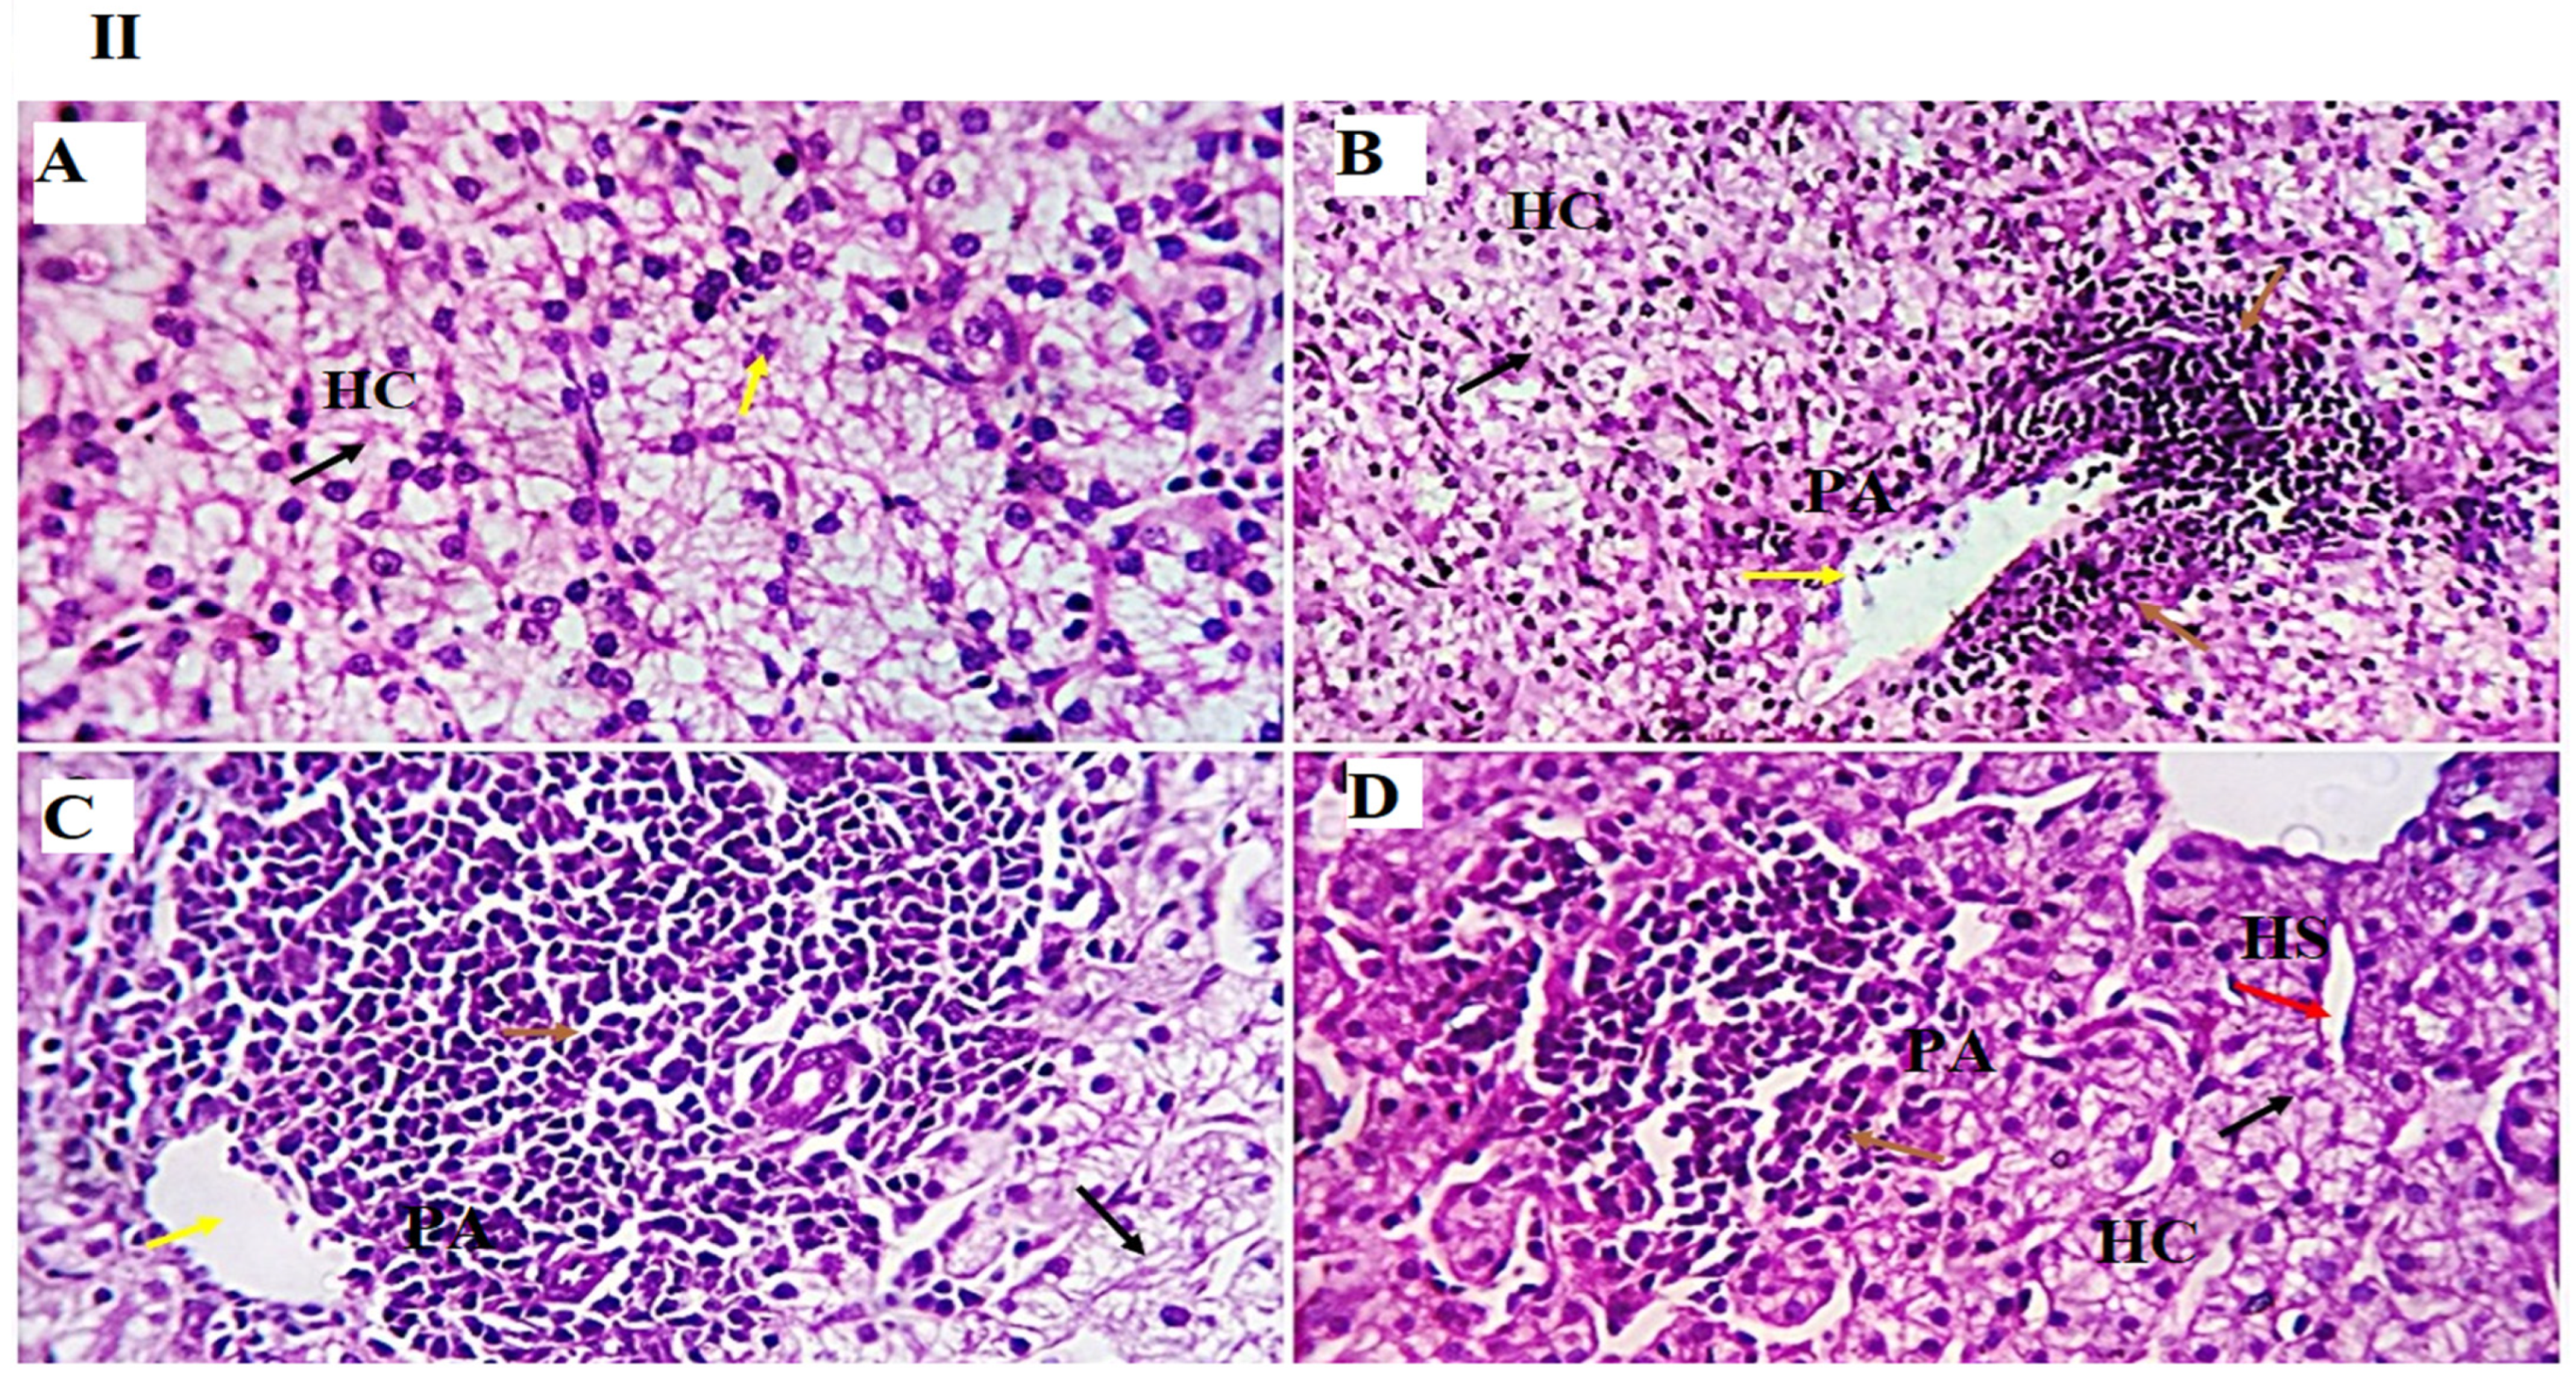

The examined liver sections from the GLC0, GLC50, GLC100, and GLC150 groups showed the standard histomorphological structure of the liver. Mild portal vascular dilatation was observed in the GLC100 group. Moderate peri-portal lymphocytic aggregation were observed in GLC50, 100, and 150 (Figure 1I,II)).

Figure 1.

(I,II). Photomicrographs from the liver ((I): H&E × 100 magnification, (II): H&E × 400 magnification) of chicken fed diet supplemented with 0 mg/kg (A), 50 mg/kg (B), 100 mg/kg (C), and 150 mg/kg (D) of GLC showing standard histological structure, including the portal area (PA, yellow arrow), hepatocytes (HC, black arrow) noted as a small mass around the central veins (CV), and a few to moderate round cells observed as a natural immune response around the portal area (PA, arrow). The 150 mg/kg group showed mild dilation of hepatic sinusoids (HS, red arrow).

Regarding the liver and kidney function tests, the current study showed that the GLC150 group had higher serum ALT and uric acid levels, while their levels did not stray from the normal levels [50]. Moreover, no differences in serum AST and creatinine levels were noted between the groups. These results may be attributed to the mild inflammatory responses caused by the highest level of GLC (150 mg kg−1), as observed in the results of the liver histopathological examination, where normal liver histoarchitecture was found in all experimental groups with mild portal vascular dilatation and lymphoplasmacytic aggregations in the GLC100 group. A minimal number of inflammatory cells were recorded in the GLC0 and GLC50 groups. The GLC150 group showed moderate peri-portal lymphocytic aggregation.

Regarding the inflammatory responses in broiler chickens fed with a GLC-supplemented diet, the results showed increased serum levels of IL-1β and IFN-γ in the GLC-fed groups in a concentration-dependent manner. Moreover, dietary GLC supplementation increased TGF-β immunoexpression in chicken liver and spleen tissues in a concentration-dependent manner. Proinflammatory cytokines (interferon-γ and IL-1β), which are essential immune proteins, are endogenous signaling molecules that facilitate cellular defense against inflammatory response [55]. Broiler chickens fed diets supplemented with GLC showed improved cell-mediated [41,56] and humoral immune responses [15,16]. The ability of GLC to enhance the immune response establishes their possible use as an antibiotic alternative by preventing numerous economically critical pathogens, for instance, Escherichia coli and Salmonella enterica [19,57]. GLC may activate macrophages or monocytes by inducing the major histocompatibility complex (MHC) compound [16]. Immune potentiation occurs because of this activity, which includes the activation of T-helper and natural killer cells, cytotoxic macrophages, T-cell development and differentiation, and the initiation of the alternative complement pathway [58]. The other signaling messengers, such as IL-1, IL-2, IFN-γ, and TNF-α, may also be included in the immuno-regulating system. The results of liver histopathology confirmed these findings, wherein moderate-to-high peri-portal lymphocytic aggregation was observed in the GLC100 and GLC150 groups. The accumulation of portal inflammatory cells appears to be a highly resistant and defensive mechanism rather than a destructive inflammatory process.